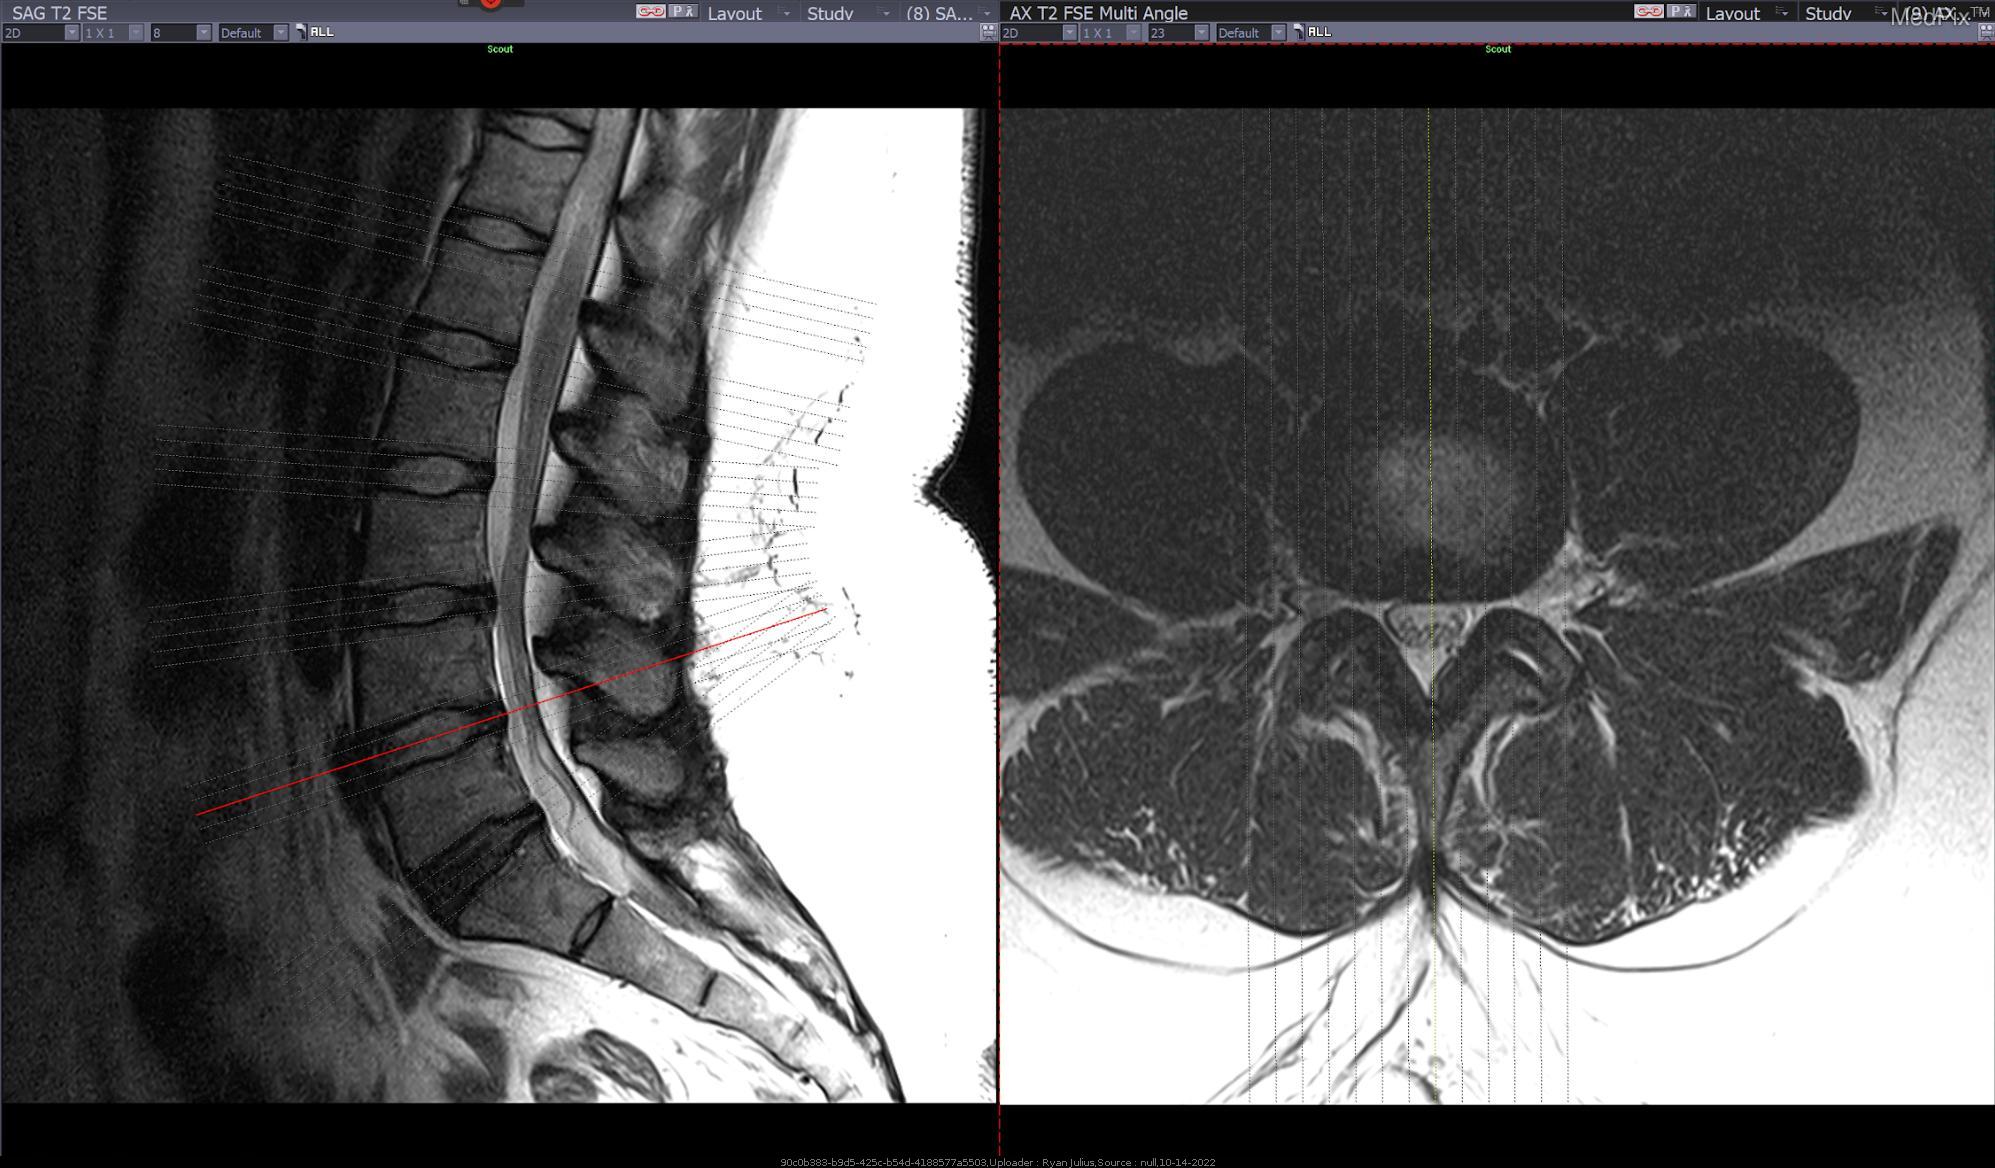

The disc is the cushion found between our spinal segments and if it undergoes trauma or repetitive overuse it can push out into the space that the nerve is causing pain into the arms if at the neck level and into the legs if in the low back area. The disc material can protrude causing nerve impingement or compression leading to decreased mobility, weakness, pain, numbness or tingling, and difficulty walking. PT can help to improve your joint stability, mobility, teach you proper body mechanics to reduce your symptoms, provide traction to decompress, improve your strength and allow for your body to reabsorb the misplaced disc material. At times surgery is required for disc issues and PT can help both pre and post surgery to improve your function.